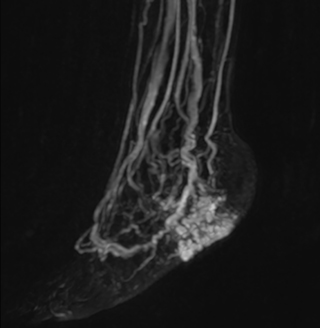

MRA of foot with 4D-TRAK XD

The images obtained with Ingenia Ambition show large coverage and high uniform signal. More vessels are visible than in a previous exam of the same patient on Achieva. The movies show a higher temporal resolution in the Ambition acquisition than in a previous Achieva 1.5T exam. Both exams use a FOV of 300 mm and voxel height and width of 0.78 mm.

Achieva 1.5T

2:30 min. TE 1 ms, TR 4 ms

Ingenia Ambition

4D Trak XD 1:54 min. TE 1ms, TR 3ms

High temporal resolution for detailed timing in MRA

The team at Miami Cardiac & Vascular Institute also appreciates Ingenia Ambition’s capabilities for fast dynamic CE-MRA. “With 4D TRAK XD, we get much better temporal and spatial resolution. Previously, with the Achieva we needed 6 seconds per dynamic, but now we can shorten that to 2 seconds per dynamic,” Avila says. “As a result, we can see the transition from arterial to venous phase with much higher temporal resolution. This is important, for example, for imaging arteriovenous malformations, which are quite vascular.”

“On our previous system we really had to sacrifice image resolution to get to 5- or 6-second temporal resolution, while now – using 4D TRAK XD on Ambition – we no longer have to sacrifice image quality,” Dr. Peña says.